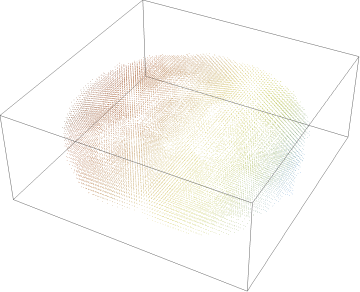

We begin by loading in the individual voxel data for the 9 participants, with a discrete plot of the points and voxel visualization for first participant:

In[]:=

VoxelData1=CloudImport["https://www.wolframcloud.com/obj/29f8f781-706c-4019-9dfc-e3dac59d67e8"];​​ListPointPlot3D[VoxelData1,ColorFunction->ColorData["SouthwestColors"],Axes->False]​​ListPlot3D[VoxelData1,ColorFunction->ColorData["SouthwestColors"],Axes->False]​​VoxelData2=CloudImport["https://www.wolframcloud.com/obj/1edbf7d6-13b6-4db5-a450-f6904fb45729"];​​VoxelData3=CloudImport["https://www.wolframcloud.com/obj/385009f7-2a28-4a41-be7e-a9e7ec74cf9b"];​​VoxelData4=CloudImport["https://www.wolframcloud.com/obj/1ce2a817-168d-4d0e-9d08-8cda7eeb4f1c"];​​VoxelData5=CloudImport["https://www.wolframcloud.com/obj/634b8283-7a7e-490b-8a8e-bc14facaf1ba"];​​VoxelData6=CloudImport["https://www.wolframcloud.com/obj/8a72681c-6441-49f3-aa1b-2a63d3e1c638"];​​VoxelData7=CloudImport["https://www.wolframcloud.com/obj/deb8610c-2397-4797-a345-e25b87e75d30"];​​VoxelData8=CloudImport["https://www.wolframcloud.com/obj/6d196cd9-164d-4fc1-9e62-2b9d98c0e7e1"];​​VoxelData9=CloudImport["https://www.wolframcloud.com/obj/d4e1a0ee-b0b8-4f82-8159-6a8ad14c95a0"];​​combinedVoxelData={VoxelData1,VoxelData2,VoxelData3,VoxelData4,​​VoxelData5,VoxelData6,VoxelData7,VoxelData8,VoxelData9};

Out[]=

We can create a list of the voxel visualizations for all 9 participants by repeating the plot function:

Map[ListPlot3D[#,ColorFunction->ColorData["SouthwestColors"],Axes->False]&,​​combinedVoxelData]